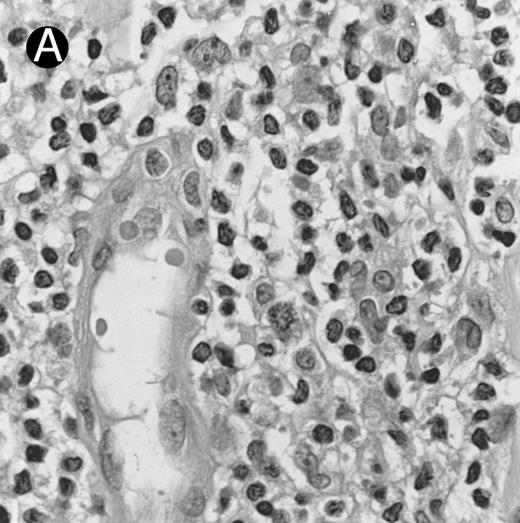

Blastoid NK cell lymphoma (case no. 40). (A) Biopsy shows a diffuse lymphomatous infiltrate with a prominent single-file pattern. (B) The neoplastic cells are medium-sized and possess fine chromatin. Mitotic figures are seen. There is remarkable resemblance to myeloid leukemic infiltration.

Blastoid NK cell lymphoma (n = 2).One patient presented with systemic disease, whereas 1 had localized disease at presentation. Histologically, the infiltrate was diffuse, with a prominent single-file pattern reminiscent of leukemia (Fig 8A). The neoplastic cells were medium-sized and had irregularly folded delicate nuclear membranes, fine chromatin, and tiny nucleoli (Fig 8B). Mitotic figures were easily identified.

In case no. 40, the immunophenotype was CD2− CD3/Leu4− CD4− CD5− CD7+ CD8− CD13− CD33+ CD56+, as analyzed on fresh tissue, and CD3ε+ (weak) CD43+ CD56+ CD68− TdT− and myeloperoxidase-negative on paraffin sections. In case no. 41, the immunophenotype as assessed on paraffin section was CD3ε+ CD43+ CD56+ TdT− and myeloperoxidase-negative. Both cases were EBERs-negative.